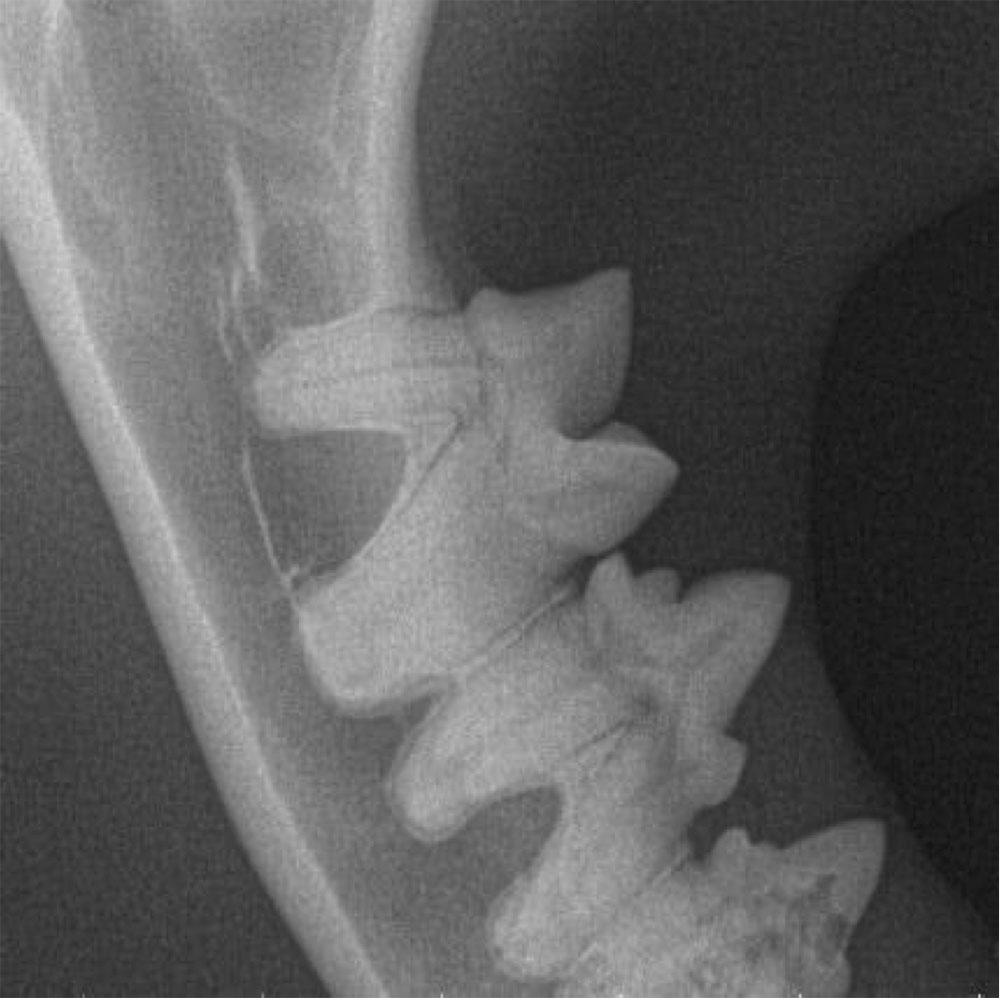

Because they start below the gum line the most sensitive way to diagnose a FORL is with radiographs, using a specialised dental X-ray system to allow us to locate and diagnose the lesions before going to surgery, minimising the risk of damage to the delicate tooth roots. FORLs may be visible above the gum line during routine examination at the vets, during dental surgery, or because an apparently healthy tooth has snapped off.

The images below are radiograph images and demonstrate how this technique is used to identify the condition. The image on the left shows healthy teeth, whereas the image on the right shows lesions and the progression of resorption.